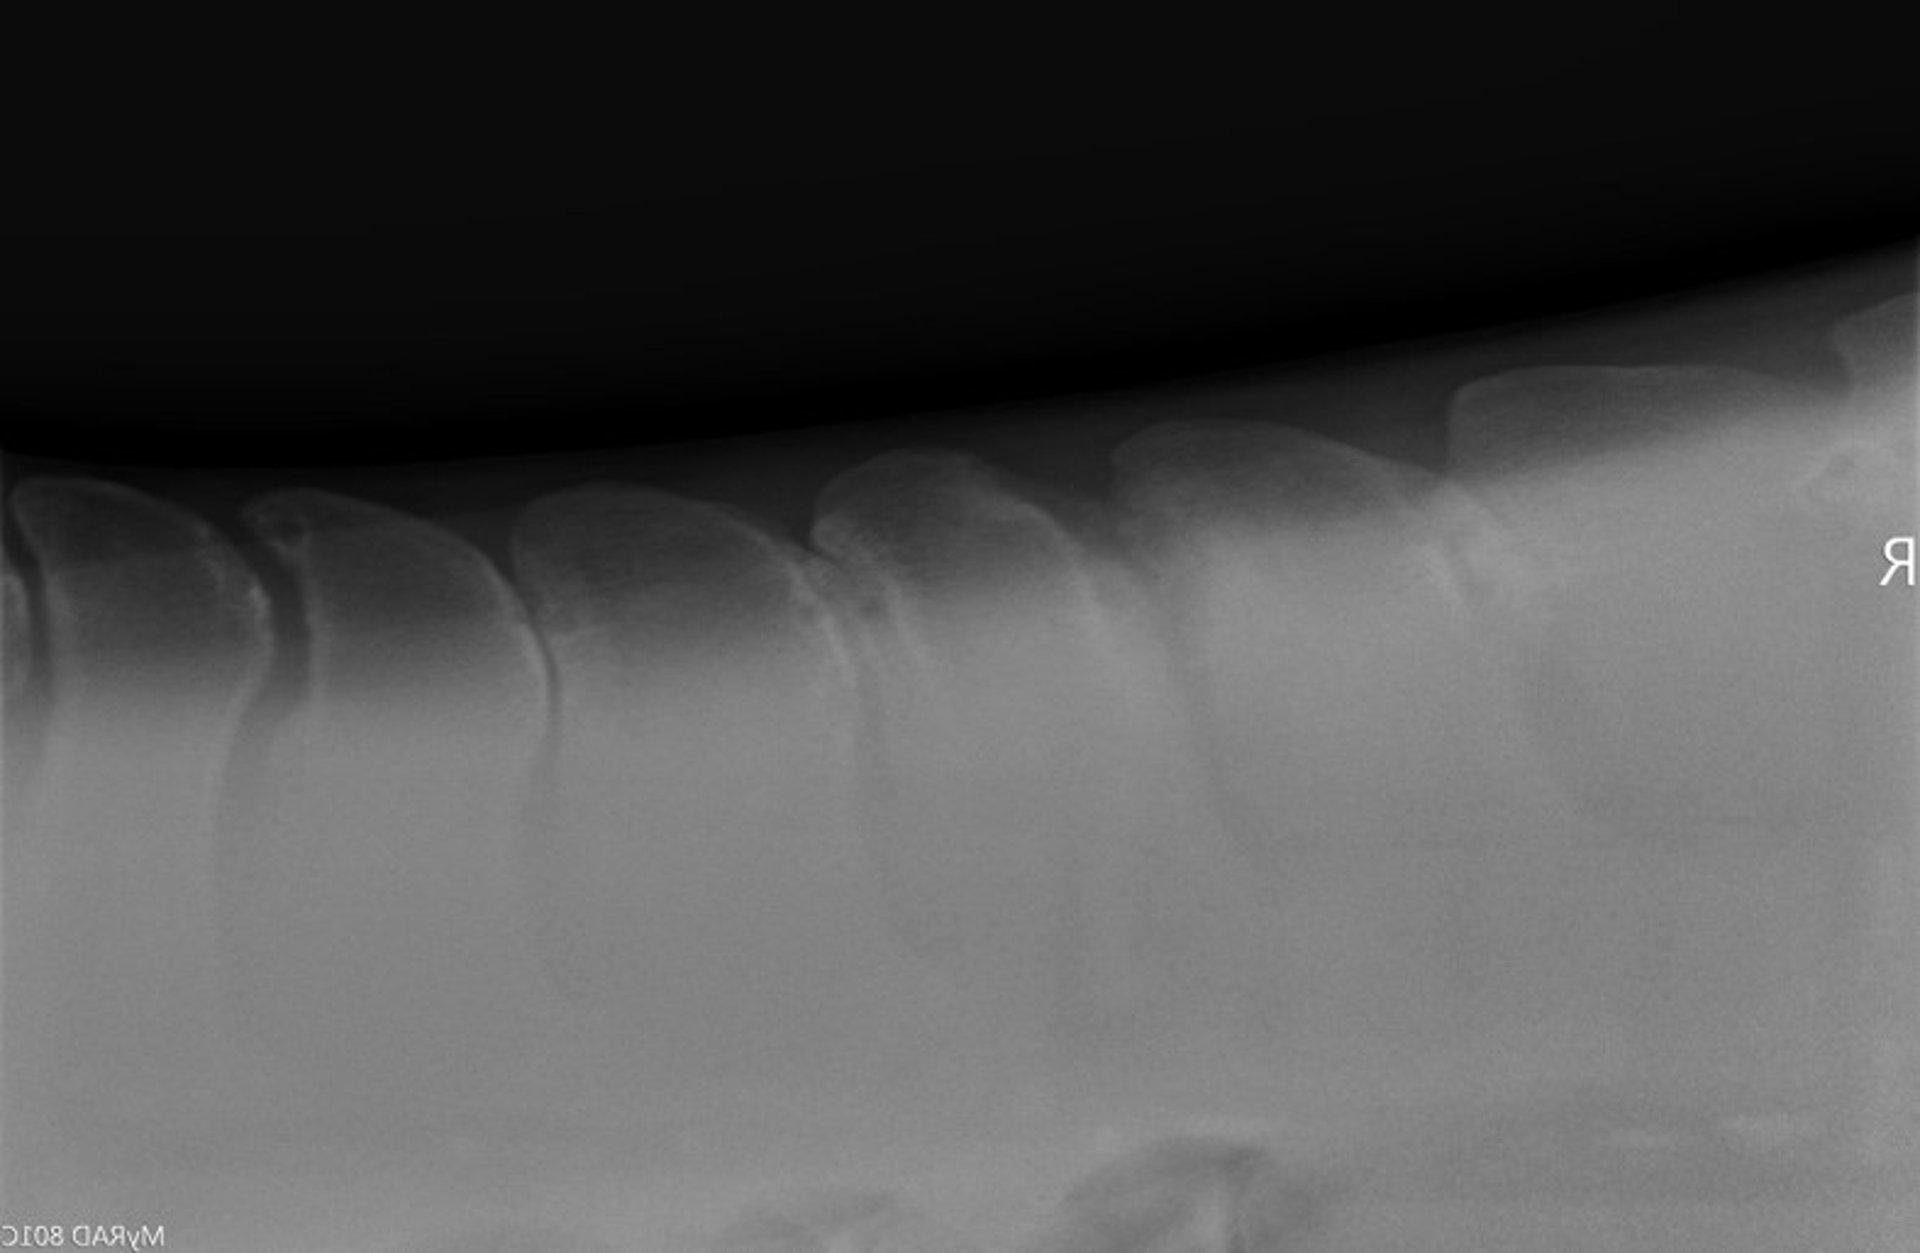

Kissing spines, radiograph, horse

Radiograph of the dorsal spinous processes in a horse, showing narrowed interspinous space and overriding dorsal spinous processes, indicating kissing spines. Sever lytic, sclerotic, and proliferative changes are evident.

Courtesy of Dr. Sushmitha Durgam.